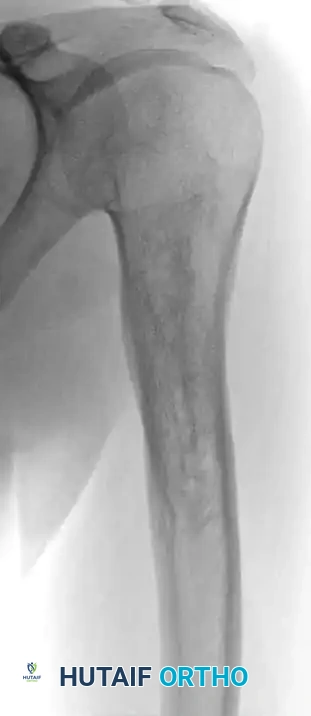

Fig. 20-21: Paget disease of the left proximal femur in a 45-year-old man. (A) Anteroposterior radiograph shows markedly coarsened trabeculae and cortical thickening. (B) Bone scan demonstrates intensely increased radiotracer uptake in the affected proximal femur.

Radiographic findings correlate directly with the disease stage. In the lytic phase, advancing osteolysis in long bones creates a classic "blade of grass" or "flame-shaped" leading edge extending from the subchondral bone toward the diaphysis. In later stages, radiographs reveal profound bony sclerosis, dramatically thickened cortices, and coarsened trabeculae, often accompanied by bowing deformities.

Bone scintigraphy (Technetium-99m) is exquisitely sensitive, showing intensely "hot" lesions. Occasionally, the combination of aggressive plain radiographic features and a positive bone scan may mimic a primary bone sarcoma. In these instances, MRI is an invaluable diagnostic tool; despite the chaotic remodeling, the marrow signal in uncomplicated Paget disease typically remains normal (isointense to fat).